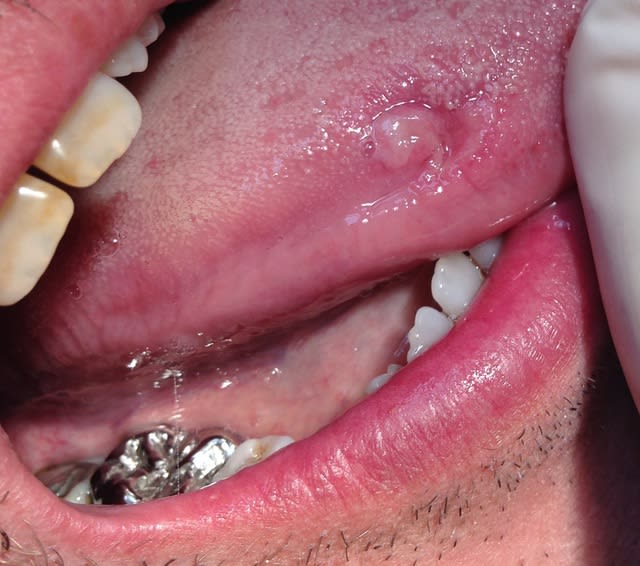

Petite devinette:

Patient 45 ans, fumeur, "monde de la nuit".

Lésion langue douloureuse depuis 3 mois, adénopathie bilatérale.

Occlusion "lol" avec en OIM, un seul contact de chaque coté sur les 7, entrainant des morsures fréquentes du bord de langue.

Diverses couronnes métal à l'anatomie agressive.

Qu'en dites vous ?

J'ai demandé une séro syphilitique.

oui ca ressemble a une blessure plutôt qu'a un chancre qui est souvent plus érythémateux.

De toute facon faut faire un TPHA/VDRL pour exclure.

Ca n'a pas vraiment un tete de carcinome.

Je dirais une sorte de diapneusie ou une cicat suites aux morsures.

un auto - piercing qui a mal tourné?

10 minute pour réaliser une biopsie ça mange pas de pain.